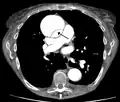

Computed tomography

Computed tomography angiography is a fast, non-invasive test that gives an accurate three-dimensional view of the aorta. These images are produced by taking rapid, thin-cut slices of the chest and abdomen, and combining them in the computer to create cross-sectional slices. To delineate the aorta to the accuracy necessary to make the proper diagnosis, an iodinated contrast material is injected into a peripheral vein. Contrast is injected and the scan performed using a bolus tracking method. This type of scan is timed to injection to capture the contrast as it enters the aorta. The scan then follows the contrast as it flows through the vessel. It has a sensitivity of 96 to 100% and a specificity of 96 to 100%. Disadvantages include the need for iodinated contrast material and the inability to diagnose the site of the intimal tear.

Chest CT with descending (type B Stanford) aortic dissection (red circle)